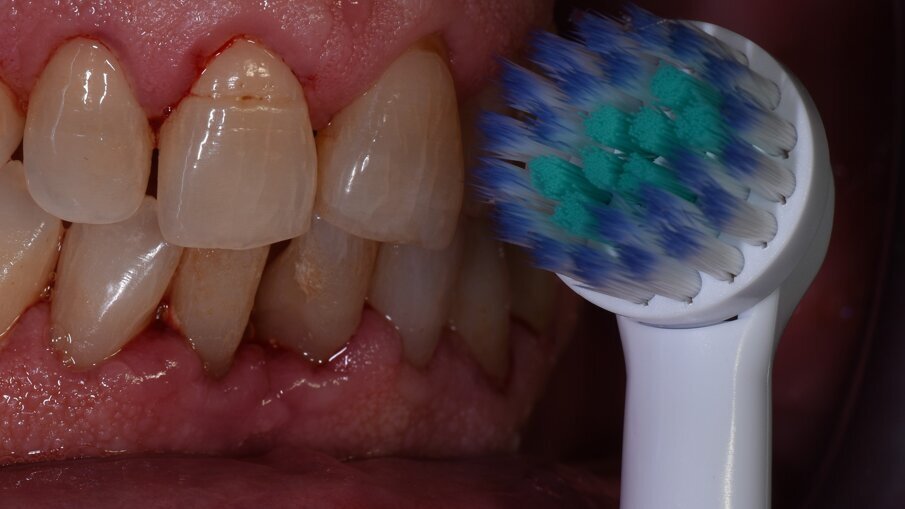

Vengono rilevati gli indici clinici e vengono condivise con il paziente le immagini raccolte con la videocamera intraorale, così da motivarlo di fronte alla presenza di tartaro e infiammazione gengivale e mostrargli le aree critiche. Viene apposto il rilevatore di placca alla fluorescina ed illuminato da una lampada fotopolimeralizzante, che permette di visualizzare la topografia del biofilm batterico (D-BIOTEK-TECNICHE)2, in modo da condividere con il paziente i siti più a rischio del cavo orale (Figg. 1a-2f).

Viene chiesto poi al paziente di provare l’utilizzo dello spazzolino GUM Technique PRO, che grazie alle setole angolate e bi-livello estremamente sottili, permette un efficace controllo del biofilm batterico anche negli spazi interprossimali. Il paziente manifesta la volontà di migliorare l’efficacia della sua routine di igiene orale domiciliare e richiede di provare uno spazzolino elettrico, proprio perché convinto di poter disorganizzare la placca con il maggior tempo a disposizione durante la sera. Effettuiamo una prova con lo spazzolino elettrico GUM PowerCAR ed il paziente dichiara di apprezzare la sensazione di sollievo data dal massaggio gengivale delicato operato dalle setole, anch’esse ultra-sottili (Figg. 3a-3d). Chiediamo al paziente di passare allo spazzolamento interprossimale con lo scovolino in gomma GUM SOFT-PICKS COMFORT FLEX e il paziente rimane favorevolmente colpito dalla facilità di utilizzo di questo strumento, grazie alle setole in gomma morbida che ritiene utili anche per il controllo del food-impaction (Figg. 4a-4f).